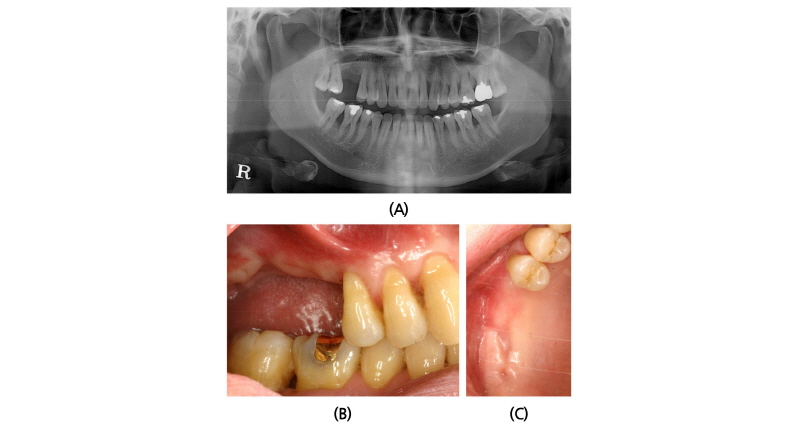

A 40-year old male patient who had missing tooth of first molar at right maxilla (#16) and discomfort of chewing in both posterior teeth visited the clinic for the periodontal treatment (Fig. 5A). Vertical tooth mobility was found on right maxillary second (#17), third molars (#18) and left maxillary first molar (#26) with severe bone loss. The patient was diagnosed as generalized chronic advanced periodontitis and #17, 18, 26 and 28 teeth were planned to be extracted. Nonsurgical periodontal treatment in whole mouth and periodontal surgeries at both mandibular posterior teeth were done. After 3 months of healing in the right maxillary edentulous area, sufficient buccopalatal width and vertical dimension about 12 mm from the soft tissue level was shown (Fig. 5B, 5C). Computed tomography revealed deficiency in the RBH with pneumatized sinus floor and horizontal bone loss especially in #17 site (Fig. 6A), which was measured to be 5 mm (Fig. 6B). The RBH of #16 sites was about 7 mm and spontaneous SFE with implant installation in both #16 and #17 using hybrid technique was planned. After flap reflection, a linear osteotomy at the lateral wall was prepared using piezoelectric device (Fig. 7A). Mesiodistal dimension of the opening was about 8 mm centered at the #17 site and slightly extended to the #16 site. The osteotomy positioned at 7~8 mm from the crest in #17 area and ran parallel along the sinus floor which had inclination from the #16 site. After detachment of the Schneiderian membrane limited in the floor, a serial drilling one step ahead of the final diameter was done with sinus elevator inserted through the lateral opening (Fig. 7B). MBCP® of 0.5 g was grafted via lateral osteotomy site and through the drilling site using osteotomes. Drilling of the final diameter was prepared and Straumann SLA® diameter 4.8 WN with 10 mm length implant was installed at both #16 and #17 (Fig. 7C). Absorbable collagen sponge (CollaTape®, Zimmer Dental, Carlsbad, CA) was covered on the lateral osteotomy site (Fig. 7D) and non-submerged healing was done (Fig. 7E). Dome-shaped sinus floor augmentation around the implant apex was shown immediately after the surgery (Fig. 8A) and prosthetic delivery was done within 3 months of healing periods. The level of SFE was maintained through 4-year of follow-up (Fig. 8B).